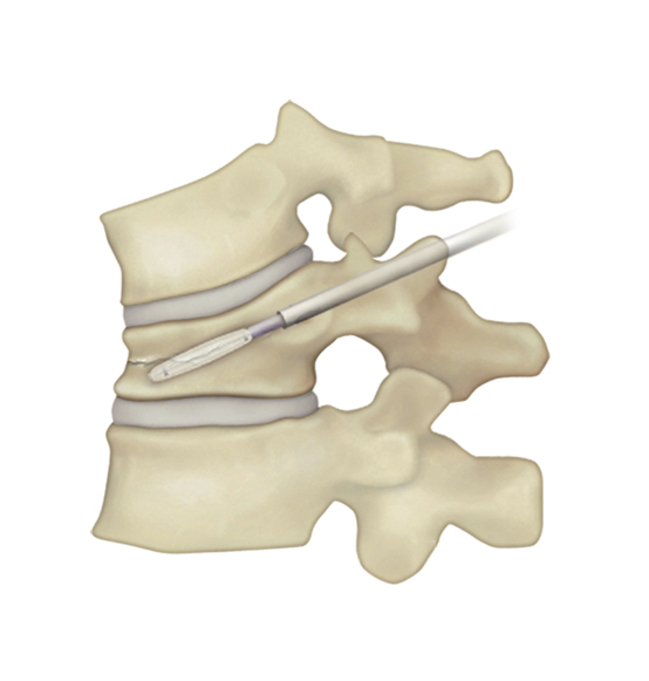

BKP治療手術の流れ

| 1)背中から針を刺入し骨折した椎体への経路を作成。小さな風船の付いた器具を挿入。 | 2)風船を徐々に膨らませつぶれた骨を持ち上げ骨折前の形に戻す。 | 3)風船を抜いて、その空間に骨セメントを充填する。 | 4)手術は約1時間程度。セメントは手術中に固まる。 |